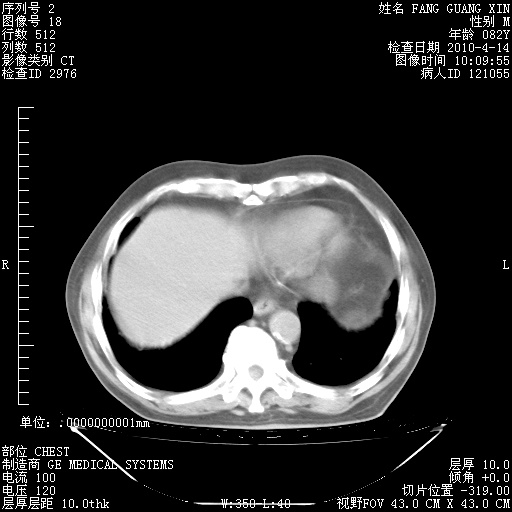

4月14日肺部CT

23.JPG

24.JPG

25.JPG

26.JPG

肺部CT平扫未见异常。